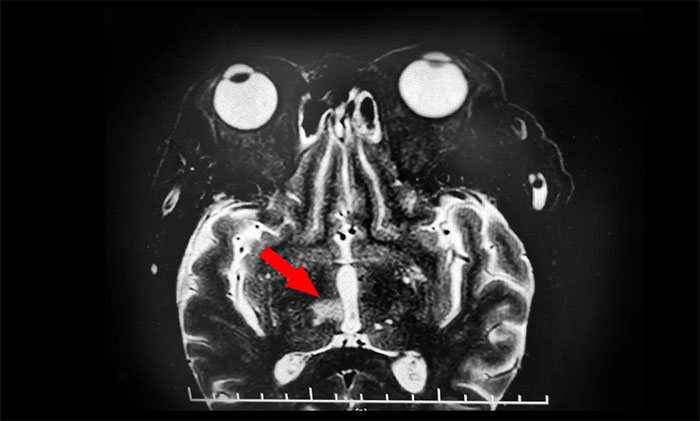

山重水復(fù)疑無(wú)路,柳暗花明又一村。隨后,為了進(jìn)一步明確患者視力不清及動(dòng)眼神經(jīng)損傷性質(zhì),張靜波主任決定為患者行眼眶核磁共振檢查。最終,患者眼框核磁發(fā)現(xiàn)端倪;颊哐劭艉舜呕貓(bào)患者腦干、丘腦梗塞灶。

再次行MR頭顱MRI平掃+增強(qiáng)+DWI+MRA,提示腦干、右側(cè)丘腦及雙側(cè)大腦半球白質(zhì)多發(fā)梗塞灶及缺血灶(中腦及右側(cè)丘腦梗塞急性期),右側(cè)大腦后動(dòng)脈狹窄,右MCA-M1段狹窄。至此,該患者雙側(cè)動(dòng)眼神經(jīng)損傷原因診斷明確,病因?yàn)橛覀?cè)中腦梗死所致,責(zé)任血管為右PCA-P1的狹窄致中腦旁正中動(dòng)脈閉塞,為動(dòng)眼紅核綜合征,導(dǎo)致同側(cè)動(dòng)眼神經(jīng)麻痹伴對(duì)側(cè)肢體共濟(jì)失調(diào),同時(shí)累及右丘腦旁正中動(dòng)脈。

▲ 眼眶核磁發(fā)現(xiàn)腦干、丘腦梗塞灶